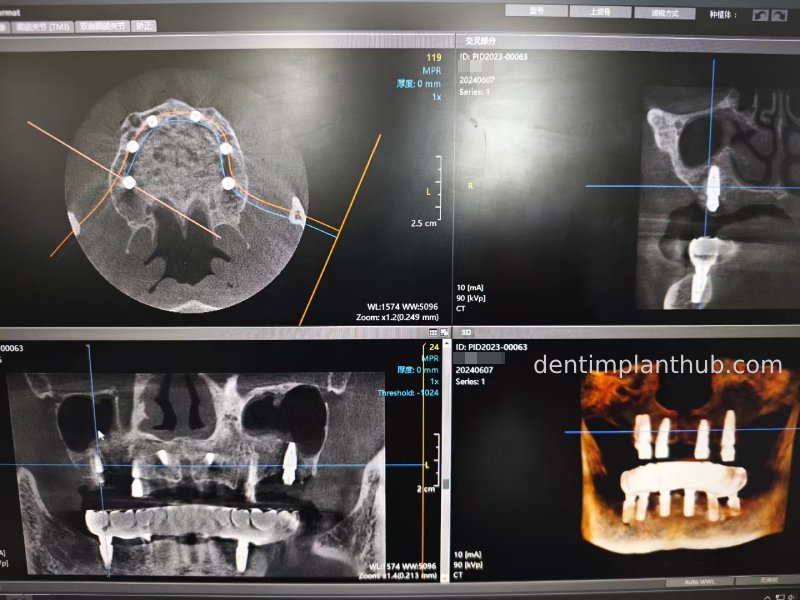

CBCT review results on 13 May '24

46

44

42

32

34

36

Maxillary condition as shown by CBCT on 13/5/24

16

14

12

22

24

26